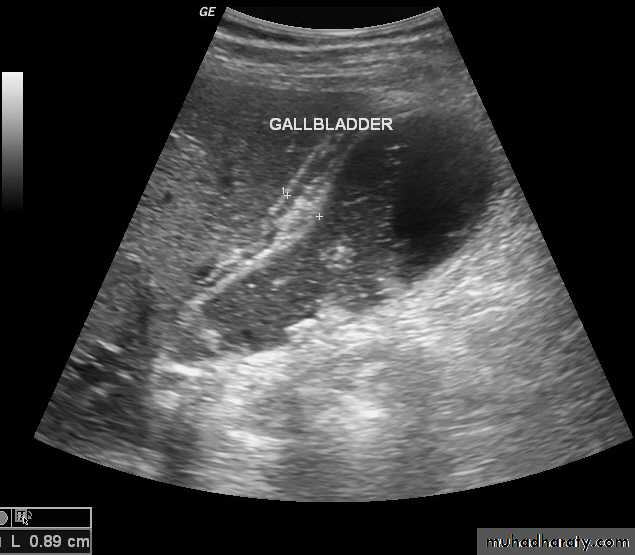

Gall bladder ,biliary tree

CBD not > 7mmnormal intrahepatic tree is too small to seen

• no contrast.Gall stone & cholecystitis